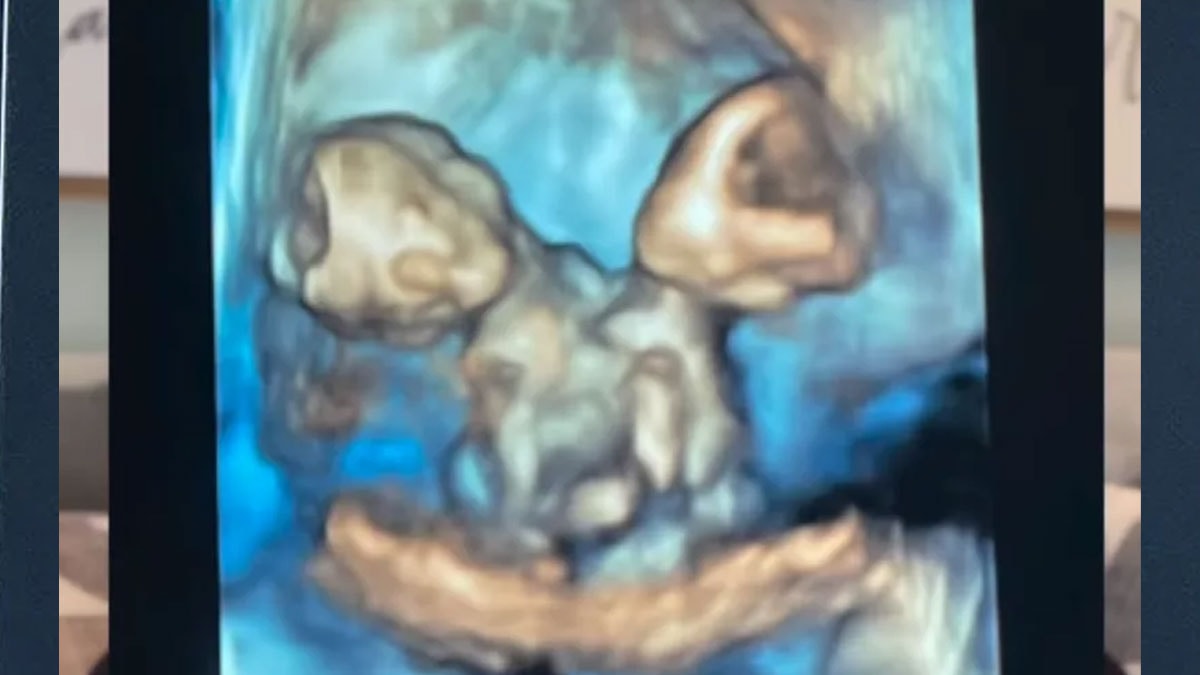

Kısa süre sonra Nicole, şiddetli karın ağrısıyla hastaneye kaldırıldığında gerçek ortaya çıktı. Anne adayı, aynı kalbi, karaciğeri, bağırsakları, diyaframı ve göbek kordonunu paylaşan ikiz kız bebeklere hamileydi.

Nicole, 32. haftada sezaryenle ikizlerini dünyaya getirdi. Maria Therese ve Rachel Clare isimleri verilen bebekler, doğum anında farklı tepkiler verdi.

"Maria yüksek sesle ağladı, Rachel ise uyuyordu. Yüzlerini görmek ve paylaştıkları bedene şahit olmak inanılmazdı" diyen anne, o anları gözyaşları içinde anlattı.